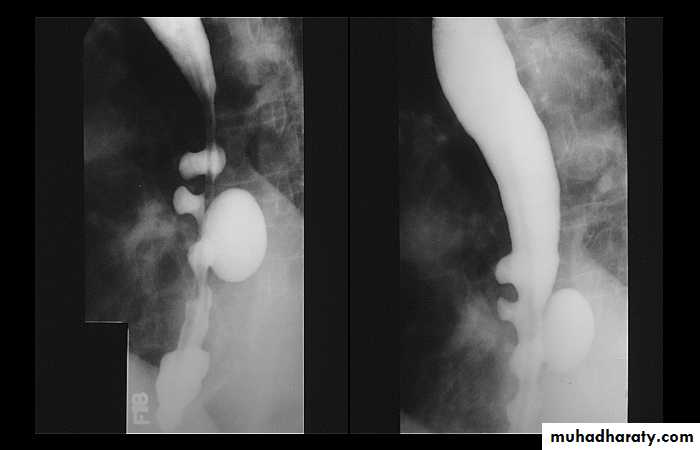

Sliding herniaOn the left initially, GE junction is below the esophageal hiatus. Later, stomach protrudes through hiatus

Para esophageal hernia

On the far left gas filled gastric funds (asterisk) protrudes through hiatus but GE junction (arrow) is below diaphragmThin mucosal fold (membrane)